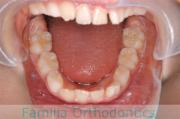

上顎

下顎

前歯の関係など

右側

正面

左側